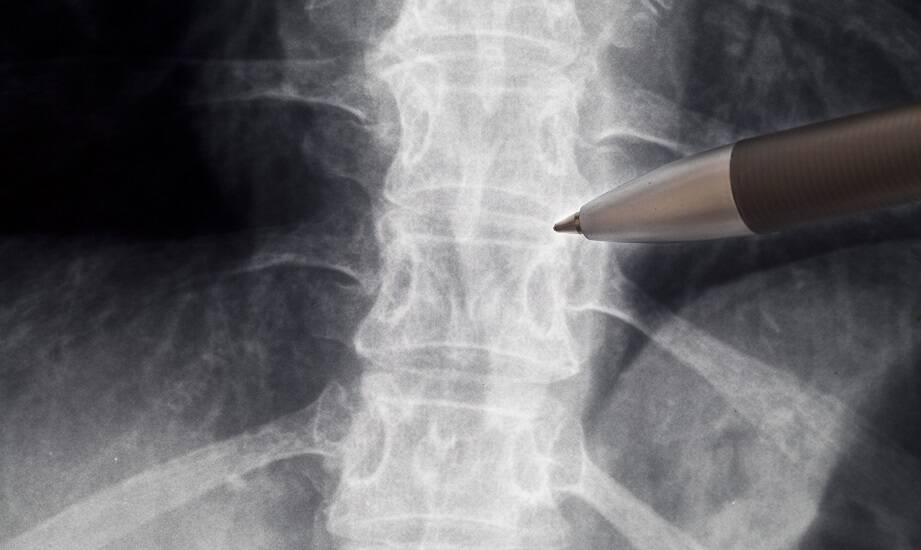

Obrazowa diagnostyka odgrywa kluczową rolę w identyfikacji schorzeń kręgosłupa, umożliwiając lekarzom dokładne zrozumienie problemów pacjentów. Dzięki nowoczesnym technikom, takim jak rezonans magnetyczny czy tomografia komputerowa, możliwe jest uzyskanie szczegółowych informacji o stanie kręgosłupa. Wprowadzenie tych metod diagnostycznych zmieniło podejście do leczenia, co pozwala na sprawniejsze i bardziej precyzyjne diagnozy. Rehabilitacja kręgosłupa w Krakowie jest realizowana z wykorzystaniem tych rozwiązań.

Interpretacja wyników badań obrazowych jest istotna w procesie leczenia schorzeń kręgosłupa. Specjaliści muszą umieć odczytywać obrazy, aby dostrzegać zmiany patologiczne, takie jak przepukliny dysków czy zwężenia kanału kręgowego. Dzięki temu mogą dobrać odpowiednie metody terapeutyczne, co ma znaczenie dla jakości życia pacjentów. Właściwe zrozumienie wyników badań ułatwia postawienie diagnozy oraz ogranicza ryzyko zastosowania nieodpowiednich lub inwazyjnych procedur. W rehabilitacji kręgosłupa w Krakowie i okolicach specjaliści współpracują z lekarzami w zakresie interpretacji badań obrazowych, co wspiera planowanie postępowania terapeutycznego.